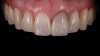

(16.) Case 2: Retracted full-smile view of the definitive all-ceramic restoration on the maxillary left central incisor.

Figure 16

Eight weeks after the initial start of the walking bleach procedure, the final layered lithium disilicate crown was tried-in and evaluated for function and esthetics. Upon patient approval, the intaglio surface of the crown was etched for 20 seconds with a 9.6% hydrofluoric acid etchant, rinsed, and then scrubbed with a 37.5% orthophosphoric acid solution to clean out any ceramic debris. The crown was then placed into an ultrasonic bath of 91% isopropyl alcohol for 5 minutes, after which the intaglio surface was coated with silane and placed under a warm air dryer for 1 minute. A translucent self-adhesive resin cement was used to bond the final restoration to the preparation. The patients both stated that they approved of the form, function, and esthetics of the definitive restoration and that they were very pleased with the final results (Figure 13 through Figure 18). Routine periodic evaluations and radiographs were scheduled to monitor their oral health and esthetics.